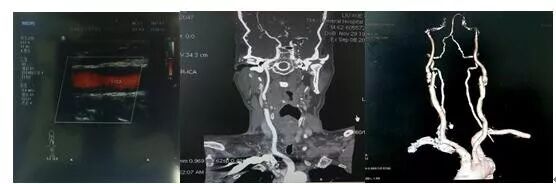

▲超声示:右侧颈内动脉重度狭窄70-90%,左侧颈内动脉轻度狭窄小于50%,颈、头CTA证实:右侧颈内动脉起始处官腔重度狭窄,左侧颈内动脉起始处,双侧颈总动脉官腔轻度狭窄